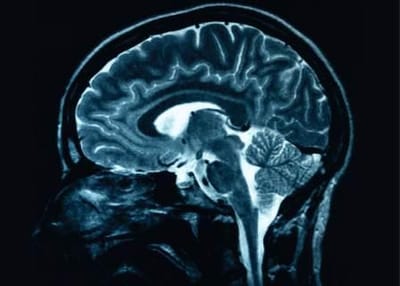

What is ABI? image

Acquired brain injury (ABI) is a term used to describe any damage to the brain that occurs after birth.

ABI can be caused by a range of factors, including stroke, infection, lack of oxygen, tumors, and traumatic brain injury. ABI can have a wide range of effects on a person's physical, cognitive, and emotional functioning, depending on the location and severity of the injury.